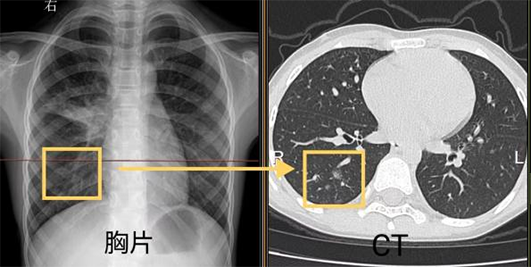

我們先通過同一個病人的胸片和胸部CT對比看一下吧。

左圖胸片黃框中的白色區(qū)域就是肺炎病灶,與右圖CT相同位置表現(xiàn)一致,但CT把病灶顯示的更清晰。